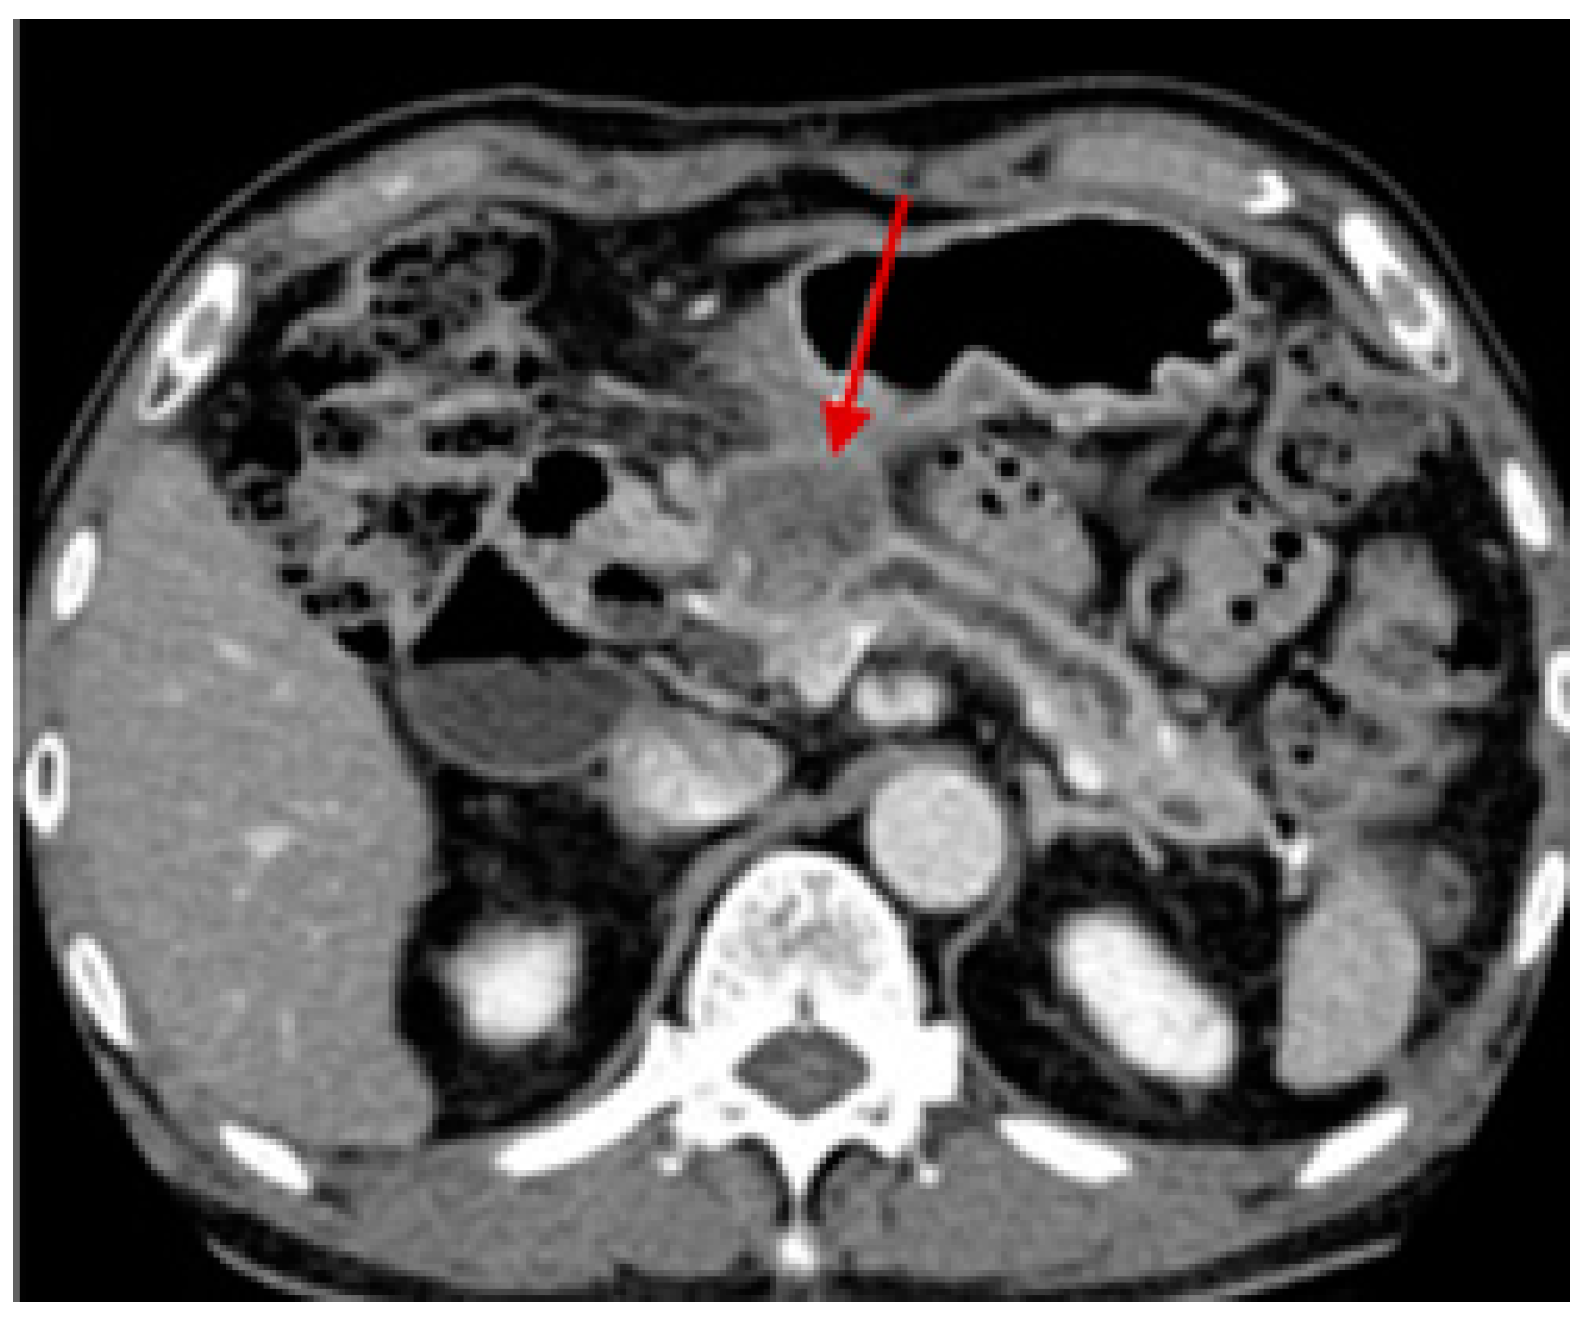

- Chu, L.C.; Singhi, A.D.; Hruban, R.H.; Fishman, E.K. Characterization of Pancreatic Serous Cystadenoma on Dual- Phase Multidetector Computed Tomography Linda. J. Comput. Assist. Tomogr. 2014, 38, 258–263. [Google Scholar] [CrossRef]

- Lee, E.S.; Lee, J.M. Imaging Diagnosis of Pancreatic Cancer: A State-of-the-Art Review. World J. Gastroenterol. 2014, 20, 7864–7877. [Google Scholar] [CrossRef] [PubMed]